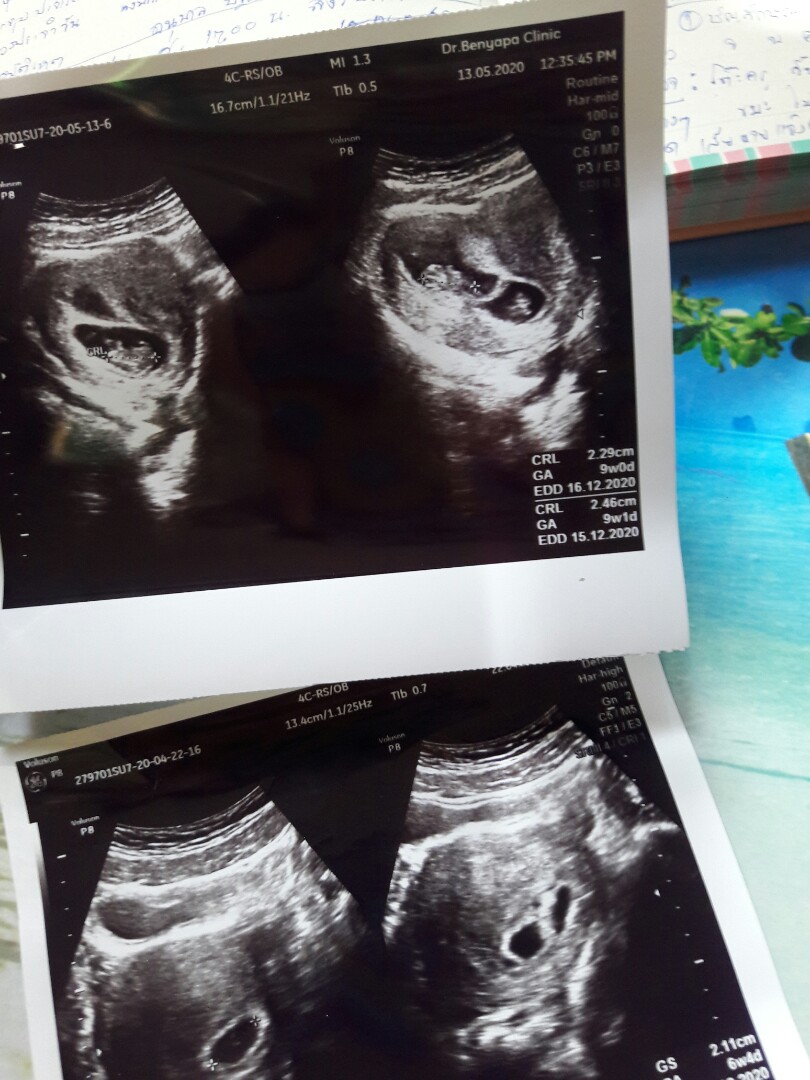

16 ธ.ค 63 ค่ะ

14 ธค ค่า♡